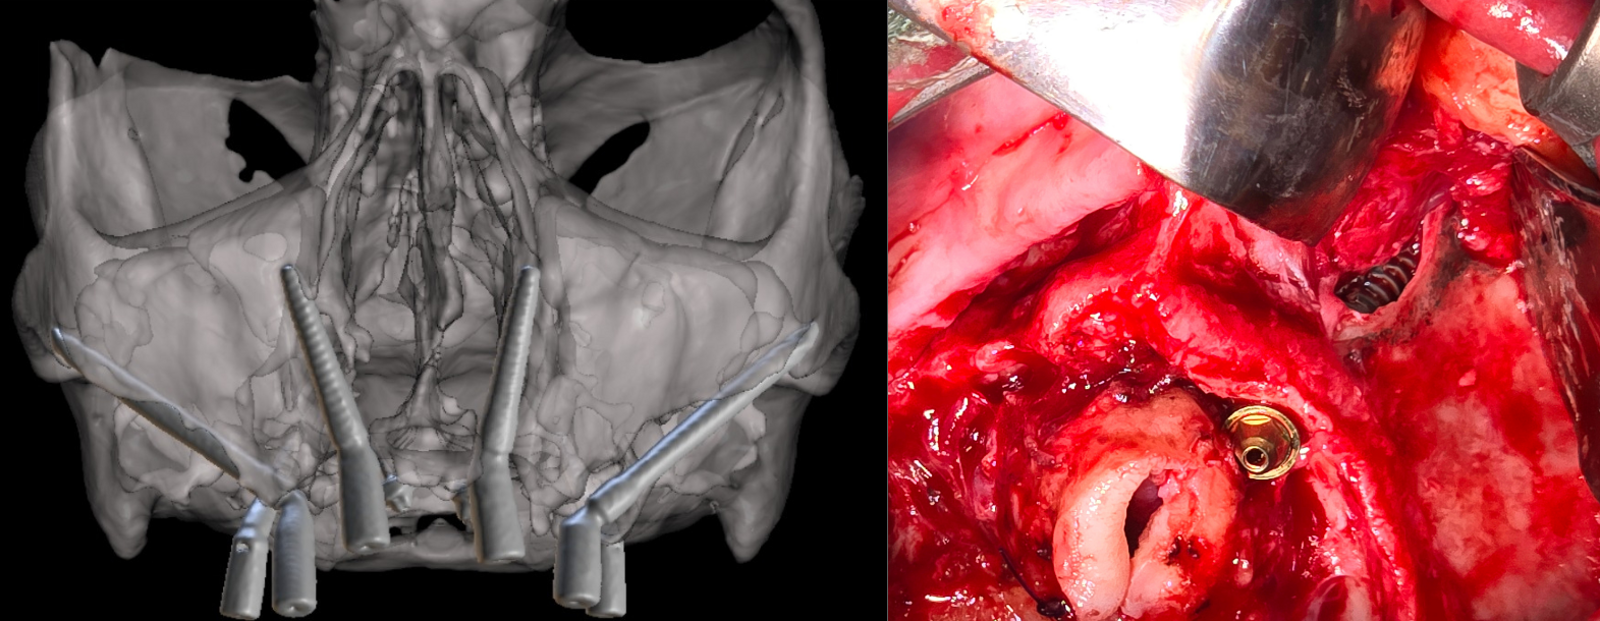

Gezien het extreem beperkte botvolume werd gekozen voor een vaste maxillaire rehabilitatie met een zygomatisch implantaatconcept, waarbij augmentatieve reconstructies werden vermeden. Met behulp van digitale planning in JDreal-software werden twee zygoma-implantaten en twee nasale/anterior-implantaten virtueel gepositioneerd (figuur 12). Op basis van deze planning werd een 3D metaal geprinte boormal ontworpen om een nauwkeurige, begeleide plaatsing volgens het geplande traject te kunnen garanderen.

Digitale planning van de implantaten (twee zygoma’s en twee nasale).

3. Chirurgische uitvoering

De chirurgie werd uitgevoerd onder lokale verdoving. Na een mid-crestale incisie werd een volledige flap opgeklapt met expositie van het zygoma. De 3D metaal geprinte boormal werd gefixeerd, waarna de implantaatkanalen werden voorbereid met een diamantboor. Vervolgens werden twee zygoma-implantaten (JD 3,9 × 37 mm) en twee nasale/anterior-implantaten (3,3 × 13 mm) geplaatst conform de digitale planning. Er werd een hoge primaire stabiliteit bereikt (>60 Ncm), waardoor directe belasting mogelijk was. In de onderkaak waren twee tissue level Straumann-implantaten geplaatst (figuur 13-15).

Postoperatieve CBCT-scan.

Chirurgische plaatsen van de implantaten.